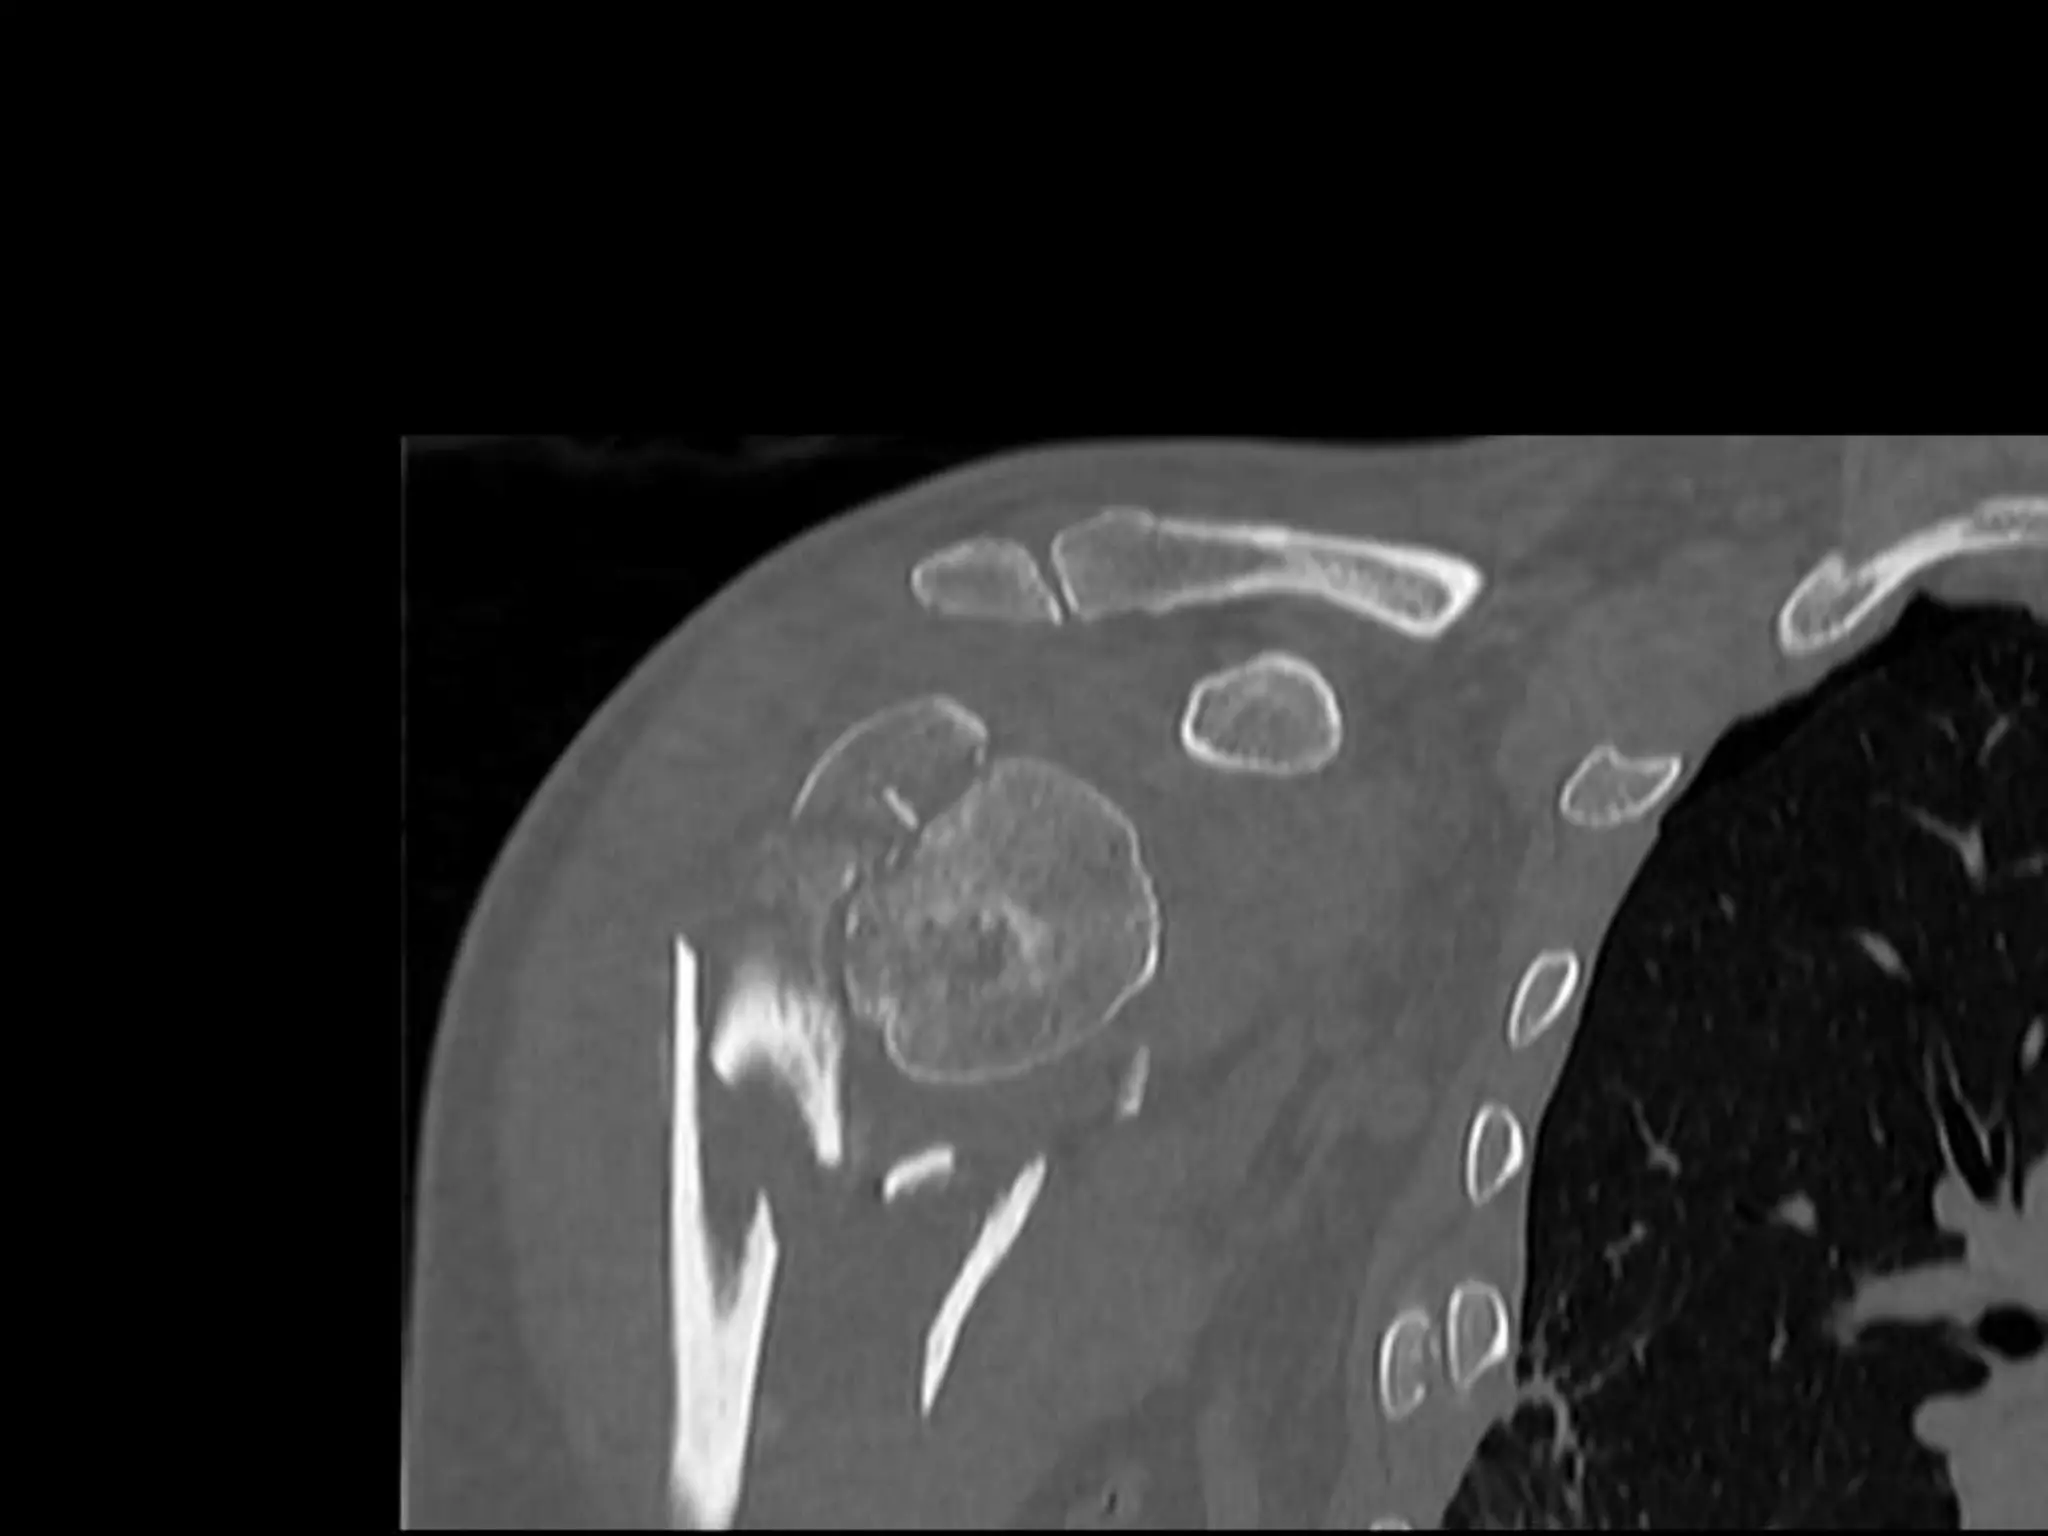

Head Ischaemia

1. Posteromedial Calcar

Predictor no 2.Medial Hinge

Medial Hinge